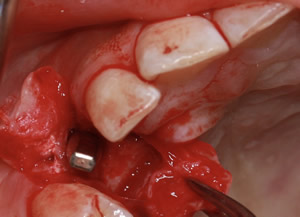

治療前

インプラント埋入時

治療後

- 年齢・性別

- 35歳男性

- 治療期間

- 3ヶ月

- 抜歯

- 右上1.3左上6.7の残根抜歯

- 治療費

- 123.2万円

- 備考

- 右上1.3左上6.7の欠損部

- 治療内容

- 4本のインプラントを一回のオペで埋入。

- 施術の副作用(リスク)

- オペによる知覚障害。インプラントによる歯肉炎。インプラント脱落。